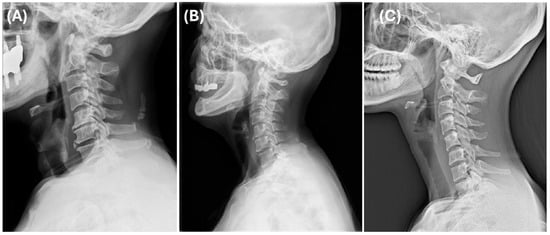

The three identified clusters represented distinct cervical sagittal alignment patterns, each with unique biomechanical characteristics. Cluster 1 showed the lowest degree of lordosis and a moderate SVA, consistent with kyphotic alignment and anterior head displacement (Figure 4A). Cluster 2 exhibited the greatest lordosis and a well-balanced cervical posture (Figure 4B). Cluster 3 was characterized by the most anteriorly displaced cervical alignment (highest SVA) along with the longest vertical and curved lengths, indicating an elongated cervical spine morphology (Figure 4C).

The standardized feature profile analysis (Figure 5) further supported these classifications, highlighting distinct sagittal alignment variations. Cluster 1 (forward-head type) demonstrated reduced lordosis and moderate SVA, suggesting a kyphotic cervical curve and anterior head posture. Cluster 2 (normal) showed the highest lordosis. Cluster 3 (long-neck type) exhibited the highest SVA and the longest cervical spine.

Cluster 1 was classified as the forward-head type, showing the lowest degree of lordosis and a moderate SVA, consistent with kyphotic alignment and anterior head displacement (Figure 4A). Cluster 2 was considered the normal type, exhibiting the greatest lordosis and a well-balanced cervical posture (Figure 4B). Cluster 3 was defined as the long-neck type, characterized by the most anteriorly displaced cervical alignment (highest SVA) along with the longest vertical and curved lengths, indicating an elongated cervical spine morphology (Figure 4C).

Figure 4. Representative lateral cervical radiographs of each cluster: (A) Cluster 1, (B) Cluster 2, and (C) Cluster 3.